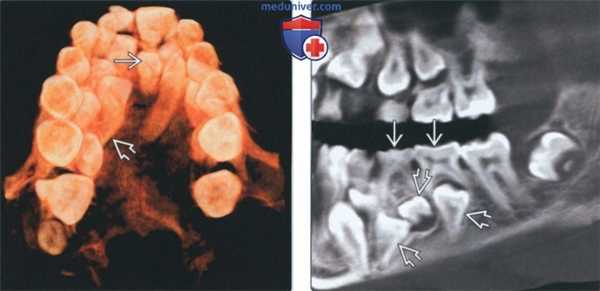

(Слева) На панорамной реформатированной КЛКТ отсутствуют второй премоляр верхней челюсти слева (временный моляр сохранен) и постоянные боковые резцы (временные зубы сохранены). Эти постоянные зубы отсутствуют чаще всего.

(Справа) На кадрированной панорамной рентгенограмме у девочки 13 лет определяется врожденное отсутствие всех зубов за исключением формирующихся третьих моляров. У этой пациентки не выявлено какое-либо наследственное заболевание; она не получала медикаментозную терапию в детстве. (Слева) На кадрированной панорамной рентгенограмме у подростка определяется врожденное отсутствие нескольких зубов, в т.ч. постоянных моляров, премоляров верхней и нижней челюсти, боковых резцов верхней челюсти.

(Справа) На кадрированной панорамной рентгенограмме у одиннадцатилетнего близнеца предыдущего пациента определяется отсутствие нескольких зубов: всех постоянных моляров, вторых премоляров, постоянных боковых резцов верхней челюсти, центральных резцов нижней челюсти. Одинаковая картина отсутствующих зубов у близнецов позволяет предположить врожденный характер.

(Слева) На панорамной реформатированной КЛКТ у пациента с расщелиной неба отсутствуют постоянные боковые резцы верхней челюсти. Отсутствие зубов на стороне поражения -частая находка, но в этом случае зубы отсутствуют и с противоположной стороны. Визуализируется временный резец с пораженной стороны.

(Справа) На панорамной рентгенограмме у девя тилетнего ребенка с эктодермальной дисплазией отсутствуют все постоянные зубы за исключением центральных резцов верхней челюсти и первых моляров нижней челюсти. (Слева) На панорамной рентгенограмме у пациента с редкой аутосомно-доминантной формой эктодермальной дисплазии (триходентальной дисплазией), проявляющейся гиподонтией, сухостью и ломкостью волос, отсутствуют несколько постоянных зубов верхней и нижней челюсти, в т.ч. моляры и премоляры.

(Справа) На кадрированной панорамной рентгенограмме у девочки 12 лет с синдромом Аксенфельда-Ритера единственные сформированные постоянные зубы - первые моляры и центральные резцы верхней челюсти.